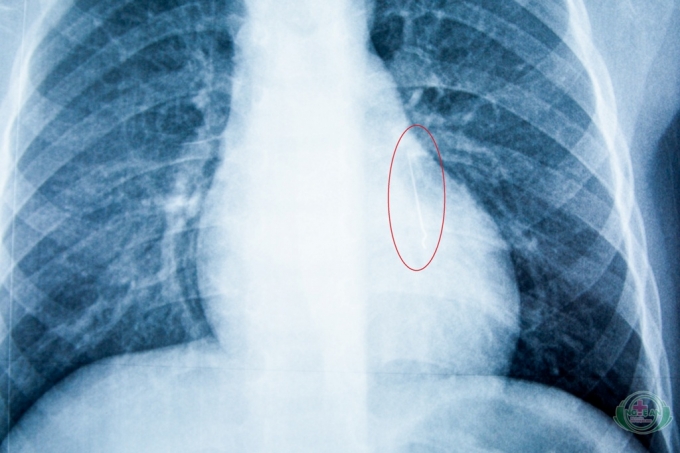

Khi chụp XQuang, các bác sĩ cũng “giật mình” khi nhận thấy có đầu kim khí nhọn nằm ở vị trí 1/3 dưới phổi của bệnh nhi.

Hình ảnh chụp XQuang cho thấy chiếc kim dài 2,5 cm nằm trong phổi của bệnh nhi.

Qua phim chụp XQuang, bác sỹ khoa tai mũi họng nhận thấy có đầu kim khí nhọn, nằm ở vị trí 1/3 dưới phổi trái của bệnh nhân. Ngay lập tức, bé K. được chuyển vào phòng mổ khoa Gây mê Hồi sức để êkip bác sỹ tiến hành gắp nội soi dị vật có gây mê.